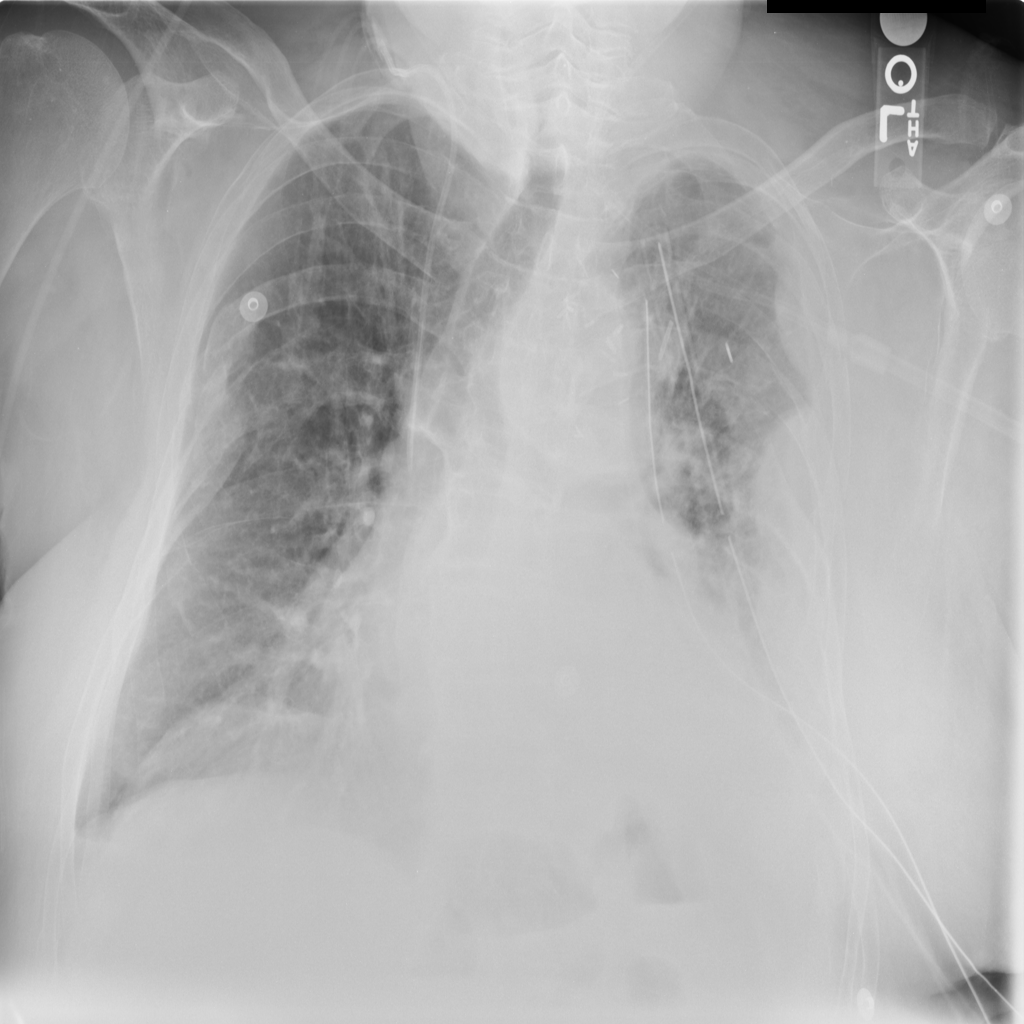

Consolidation

Consolidation refers to air-space filling that makes part of the lung appear denser on imaging.

Showing up to 90 reference images for Consolidation.

PAT-A380 · IMG-002Consolidation

PAT-A380 · IMG-002

AP